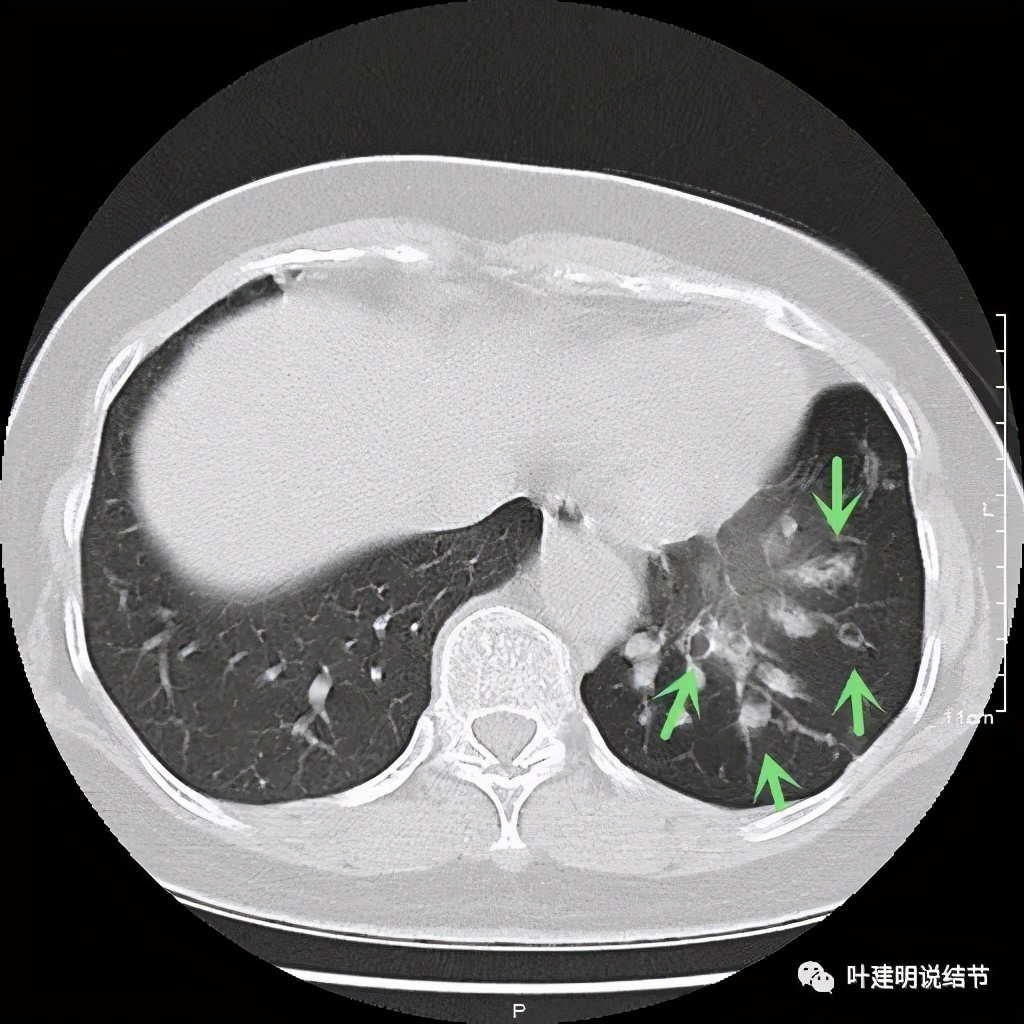

可见同样部位的左下结节已经较去年密度明显低了一些,说明有所吸收了!基本上已经只是磨玻璃密度了。那么其他病灶的情况呢?

也是有所变化,但病灶仍仍在,是异常的。最后这同图上还见到似乎也是实性伴小空腔的病灶(红色三角形标注处),是不是与之前的病灶有点像?